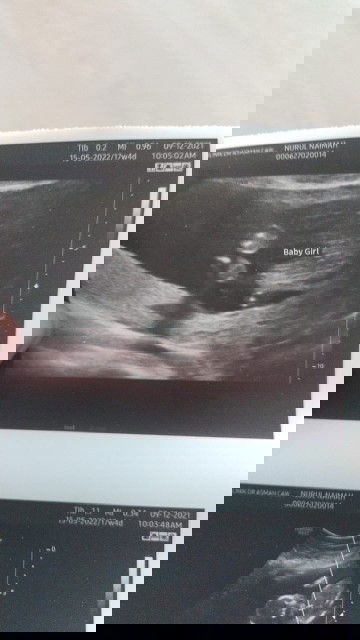

Gender baby

Assalamualaikum.betul ke bby gurl.hihi sebab anak first excited skit🤭

Klu tgk scan ni mcm obvious girl, tp boleh je scan lg 2-3 kali utk confirmkan 😊

mmg mcm girl🥰